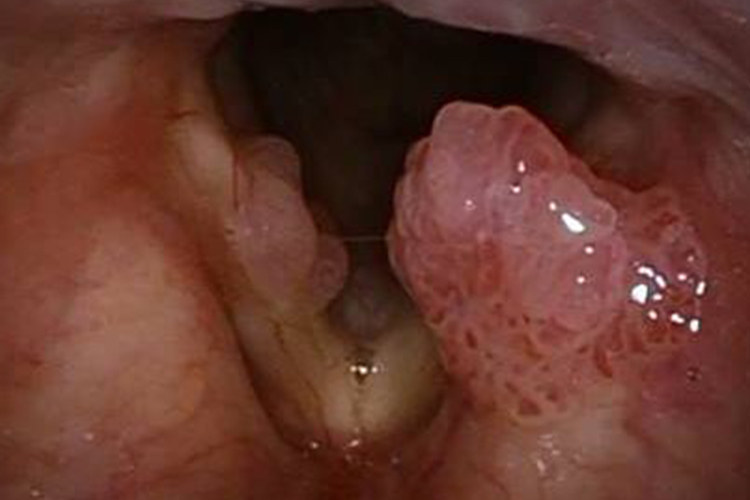

喉癌的大体病理可分为4型,如溃疡浸润型,主要表现为肿瘤组织稍向黏膜表面突出,可见向深层浸润的凹陷溃疡,边界多不整齐,界限不清;

菜花型主要呈外突状生长,呈菜花状,边界清楚;结节型或包块型的肿瘤表面为不规则隆起或球形隆起,多有较完整的被膜;

混合型兼有溃疡和菜花型的外观,表面凹凸不平,常有较深的溃疡。患者可出现声音嘶哑、咳嗽、疼痛、咽部不适、异物感、血痰或咯血、进食呛咳、呼吸困难、颈部包块等症状。